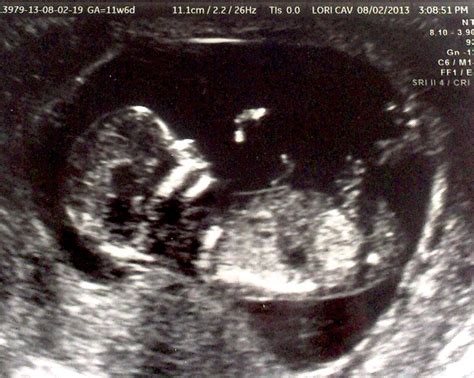

Pregnancy is an exciting journey filled with milestones, and one of the most anticipated moments is the 13 Weeks Ultrasound. This scan, typically performed between 12 and 13 weeks of gestation, offers a wealth of information about the developing fetus and the mother's health. Understanding what to expect during this ultrasound can help alleviate anxiety and prepare expectant parents for the next steps in their pregnancy journey.

A 13 Weeks Ultrasound is a routine prenatal check-up that uses high-frequency sound waves to create images of the fetus and the uterus. This scan is crucial for several reasons, including assessing the fetus's development, detecting any potential issues, and providing a clearer picture of the pregnancy timeline.

• Fetal Development Assessment: At 13 weeks, the fetus undergoes significant developmental changes. The ultrasound can confirm the fetus's age, measure the crown-rump length (CRL), and check for the presence of key structures like the heart, brain, and limbs.

• Visual Confirmation: Seeing the fetus on the ultrasound screen can be an emotional and reassuring experience. At this stage, the fetus is about the size of a plum, and its features are becoming more distinct.

• Heartbeat Detection: The ultrasound technician will listen for the fetus's heartbeat, which is usually strong and steady by this week. Hearing the heartbeat can be a comforting sign of the fetus's health.